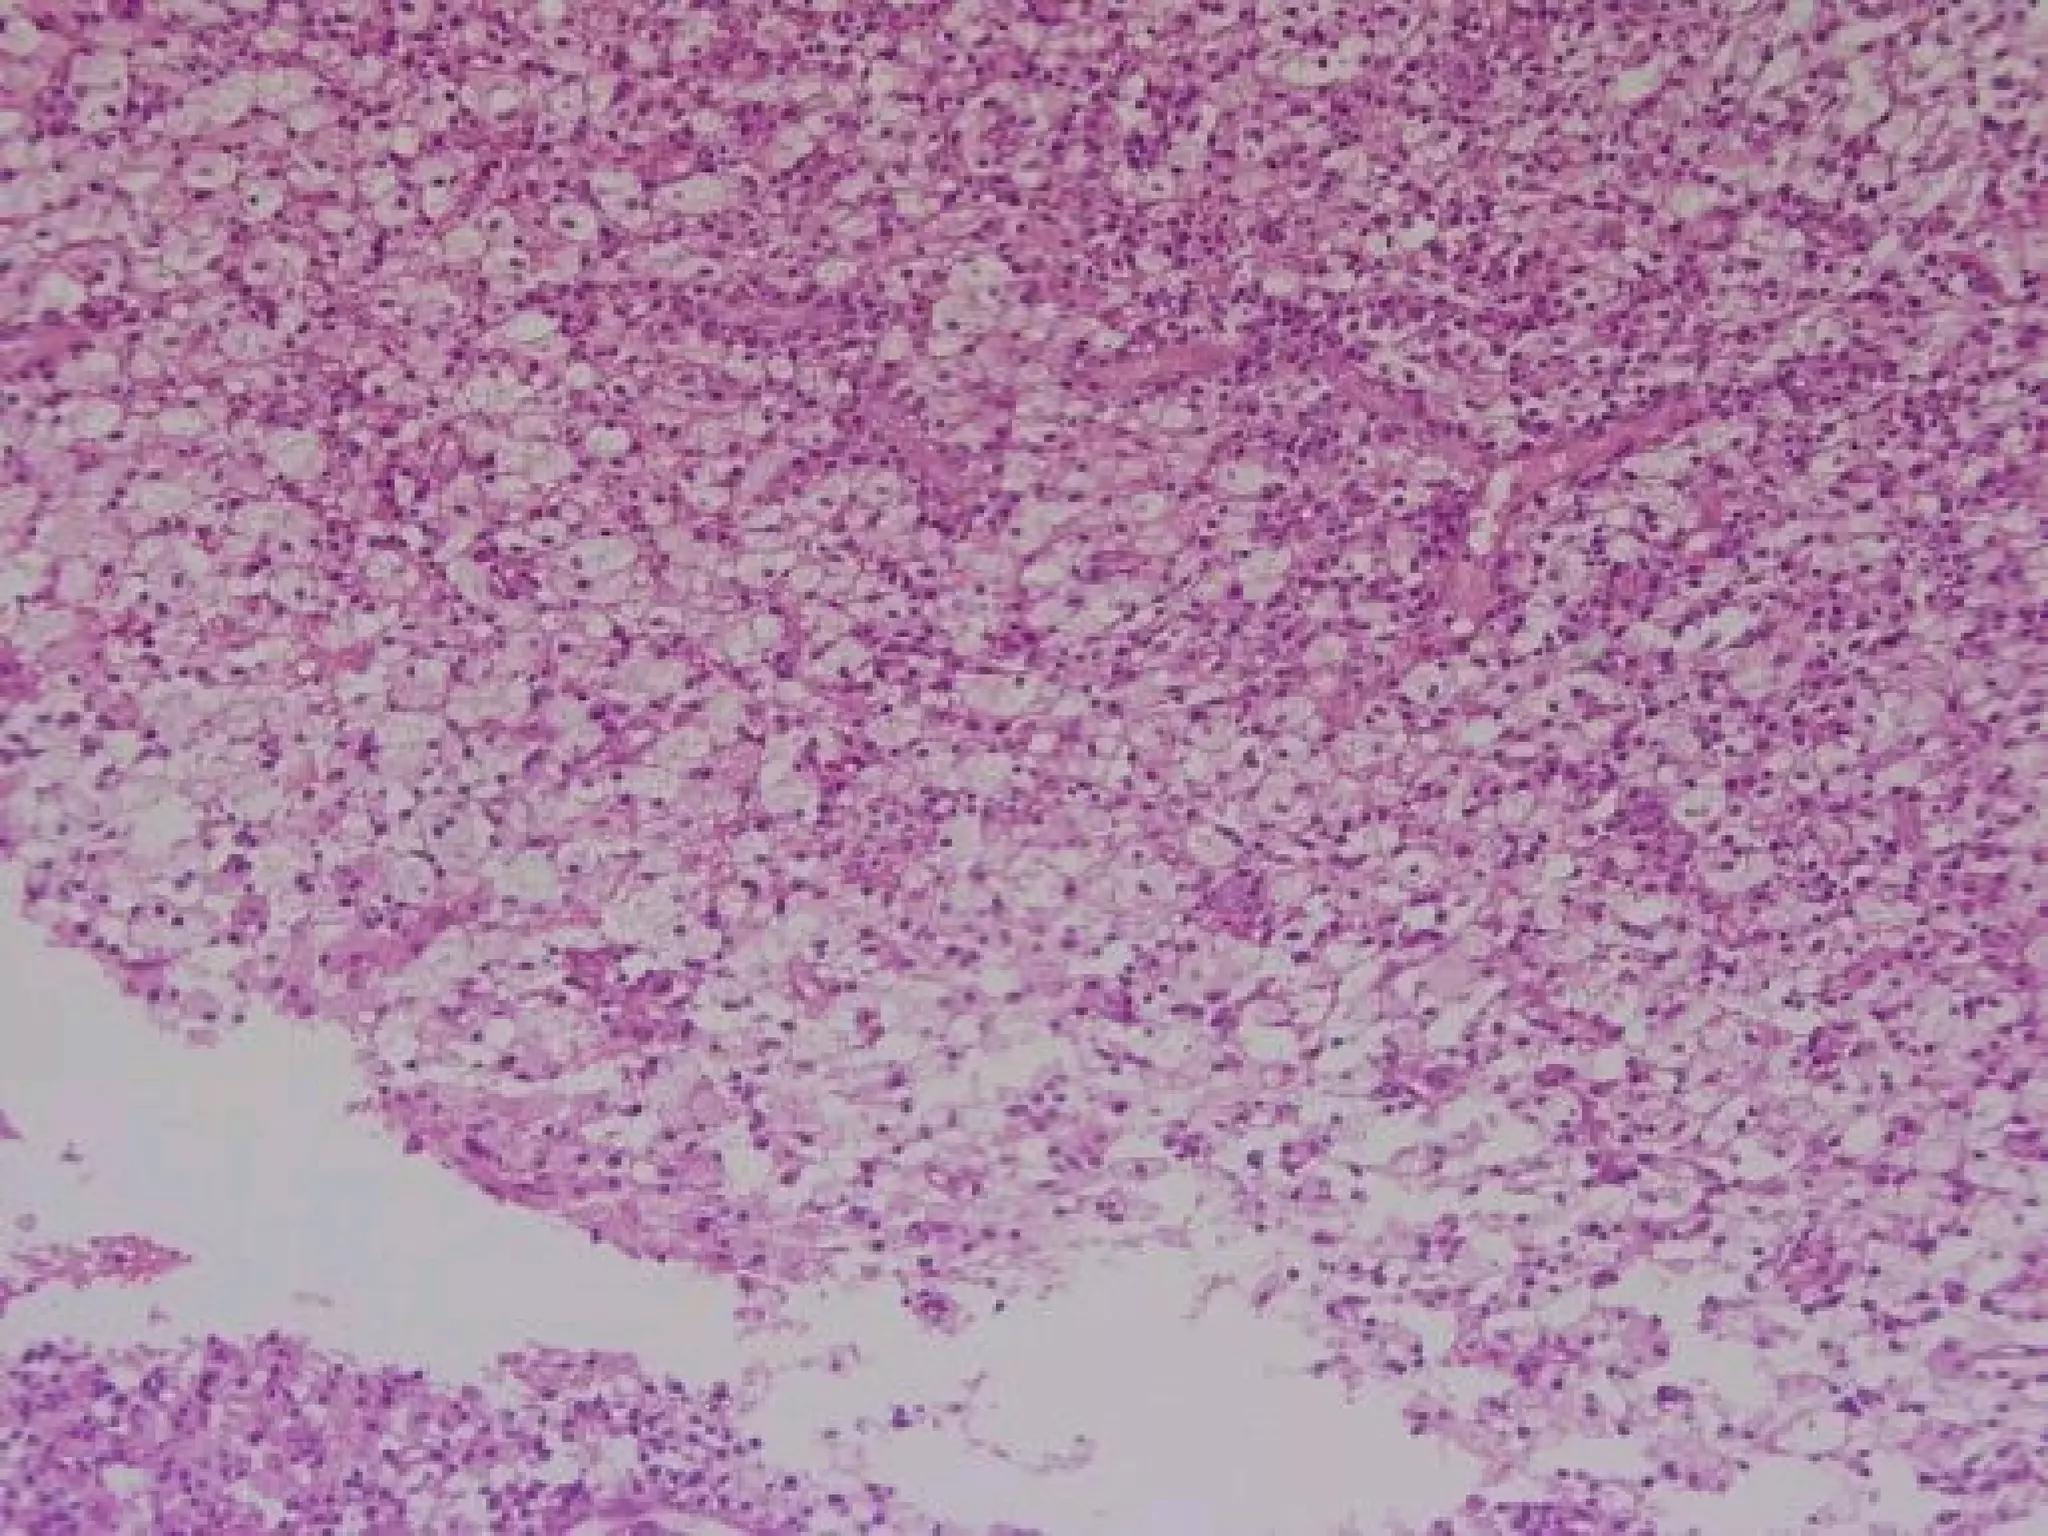

Acute Abscess

 Histopathological

Features:

Zone of liquefaction composed of:

• Exudates.

• Necrotic tissue.

• Dead neutrophils.

Dilated blood vessels.

 Inflammatory [granular cell]

infiltration.